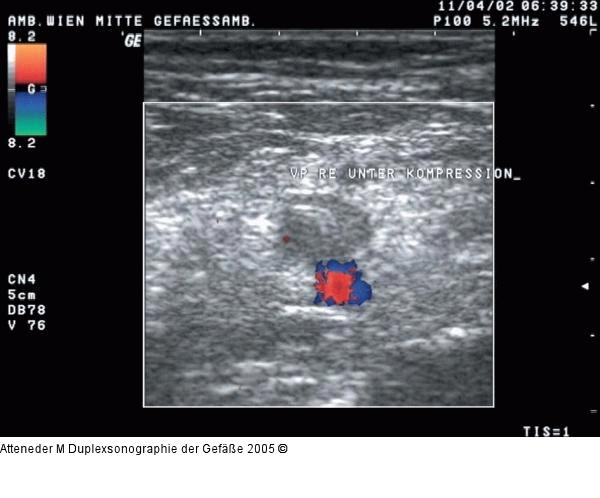

Abbildung 10: Duplexsonographie - V. poplitea - Kompression Kompressionsversuch der V. poplitea. Aufgrund der Thromben ist keine vollständige Kompression der Vene möglich. |

Kompressionsversuch der V. poplitea. Aufgrund der Thromben ist keine vollständige Kompression der Vene möglich. |